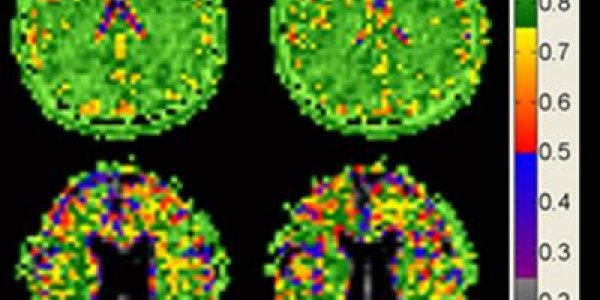

Toward Targeted Melanoma Therapies

Melanoma patients with high levels of a protein that controls the expression of pro-growth genes are less likely to survive, according to a study led by researchers at Icahn School of Medicine at…